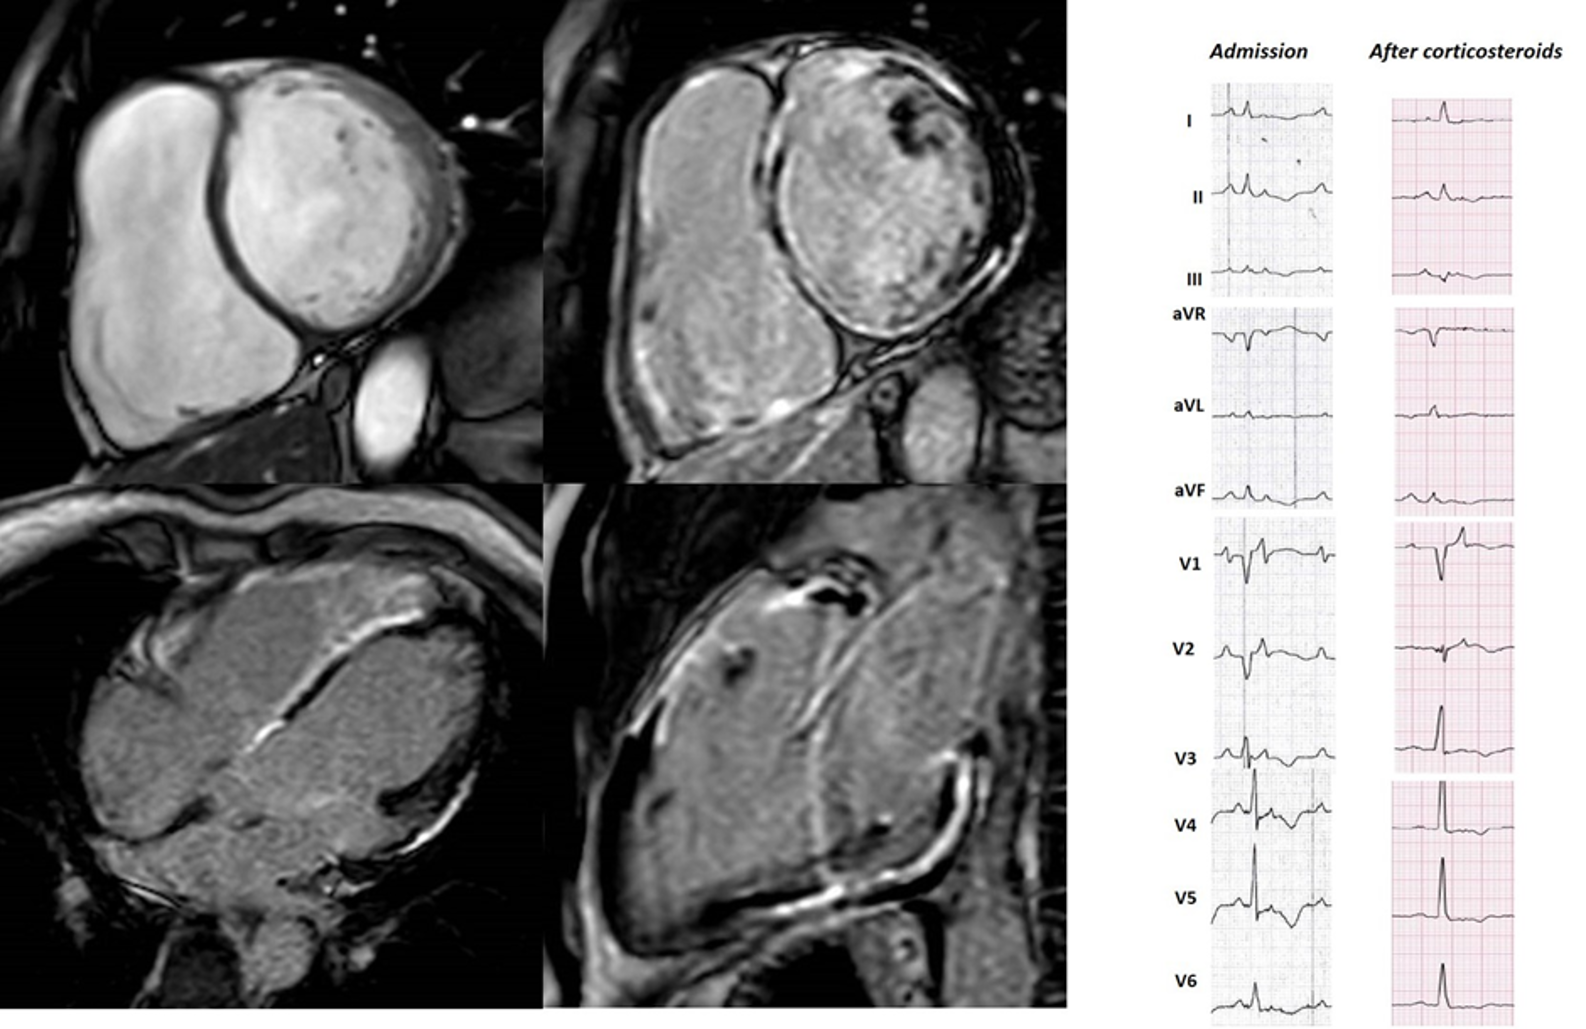

The observation of inflammatory infiltrates in up to two-thirds of autoptic ARVC diagnosis implies that inflammation may have a role in ACM pathogenesis [48]. Protonotarios et al. [49] retrospectively analysed 16 ARVC patients referred for 18F-fluorodeoxyglucose positron emission tomography (FDG-PET)—a validated technique for detecting myocardial inflammation in suspected myocarditis. Despite a few study limitations, the group proved 36% of their ARVC patients on FDG-PET had active myocardial inflammation. Inflammatory cytokines have been found at higher levels in the serum of ARVC patients. In addition, there is gathering evidence of autoimmunity [50] being involved, as inferred by the identification of anti-desmosome antibodies that could be produced by the unmasking of epitopes caused by the disease. Indeed, a myocarditis-like clinical presentation is increasingly reported in ACM patients, either being the initial trigger of the disease or a transient “hot phase” along its clinical continuum [51]. To further complicate things, there is clinical and pathological overlap between ACM and sarcoidosis, another inflammatory myocardial disease (Fig. 4) [52, 53]. Thus, ACM diagnosis remains clinical challenging both in the early stages when myopericarditis, sarcoidosis, or other inflammatory disease need to be ruled out, and at later stages when ischemic/nonischemic dilated cardiomyopathies are concerned.

Fig. 4.48 years old male, endurance sportsman, with active sarcoidosis admitted in class 4 heart failure with recurrent slow monomorphic VTs. The ECG at admission mimics ARVC with a caricatural delayed high-amplitude epsilon wave and precordial T-wave inversion resulting in QT prolongation. Clinical improvement and partial ECG modification occurred after 30 days of steroid treatment. CMR showed biventricular enlargement and systolic dysfunction, with biventricular epicardial and midventricular LGE distribution. This case highlights the diagnostic challenges in ACM.